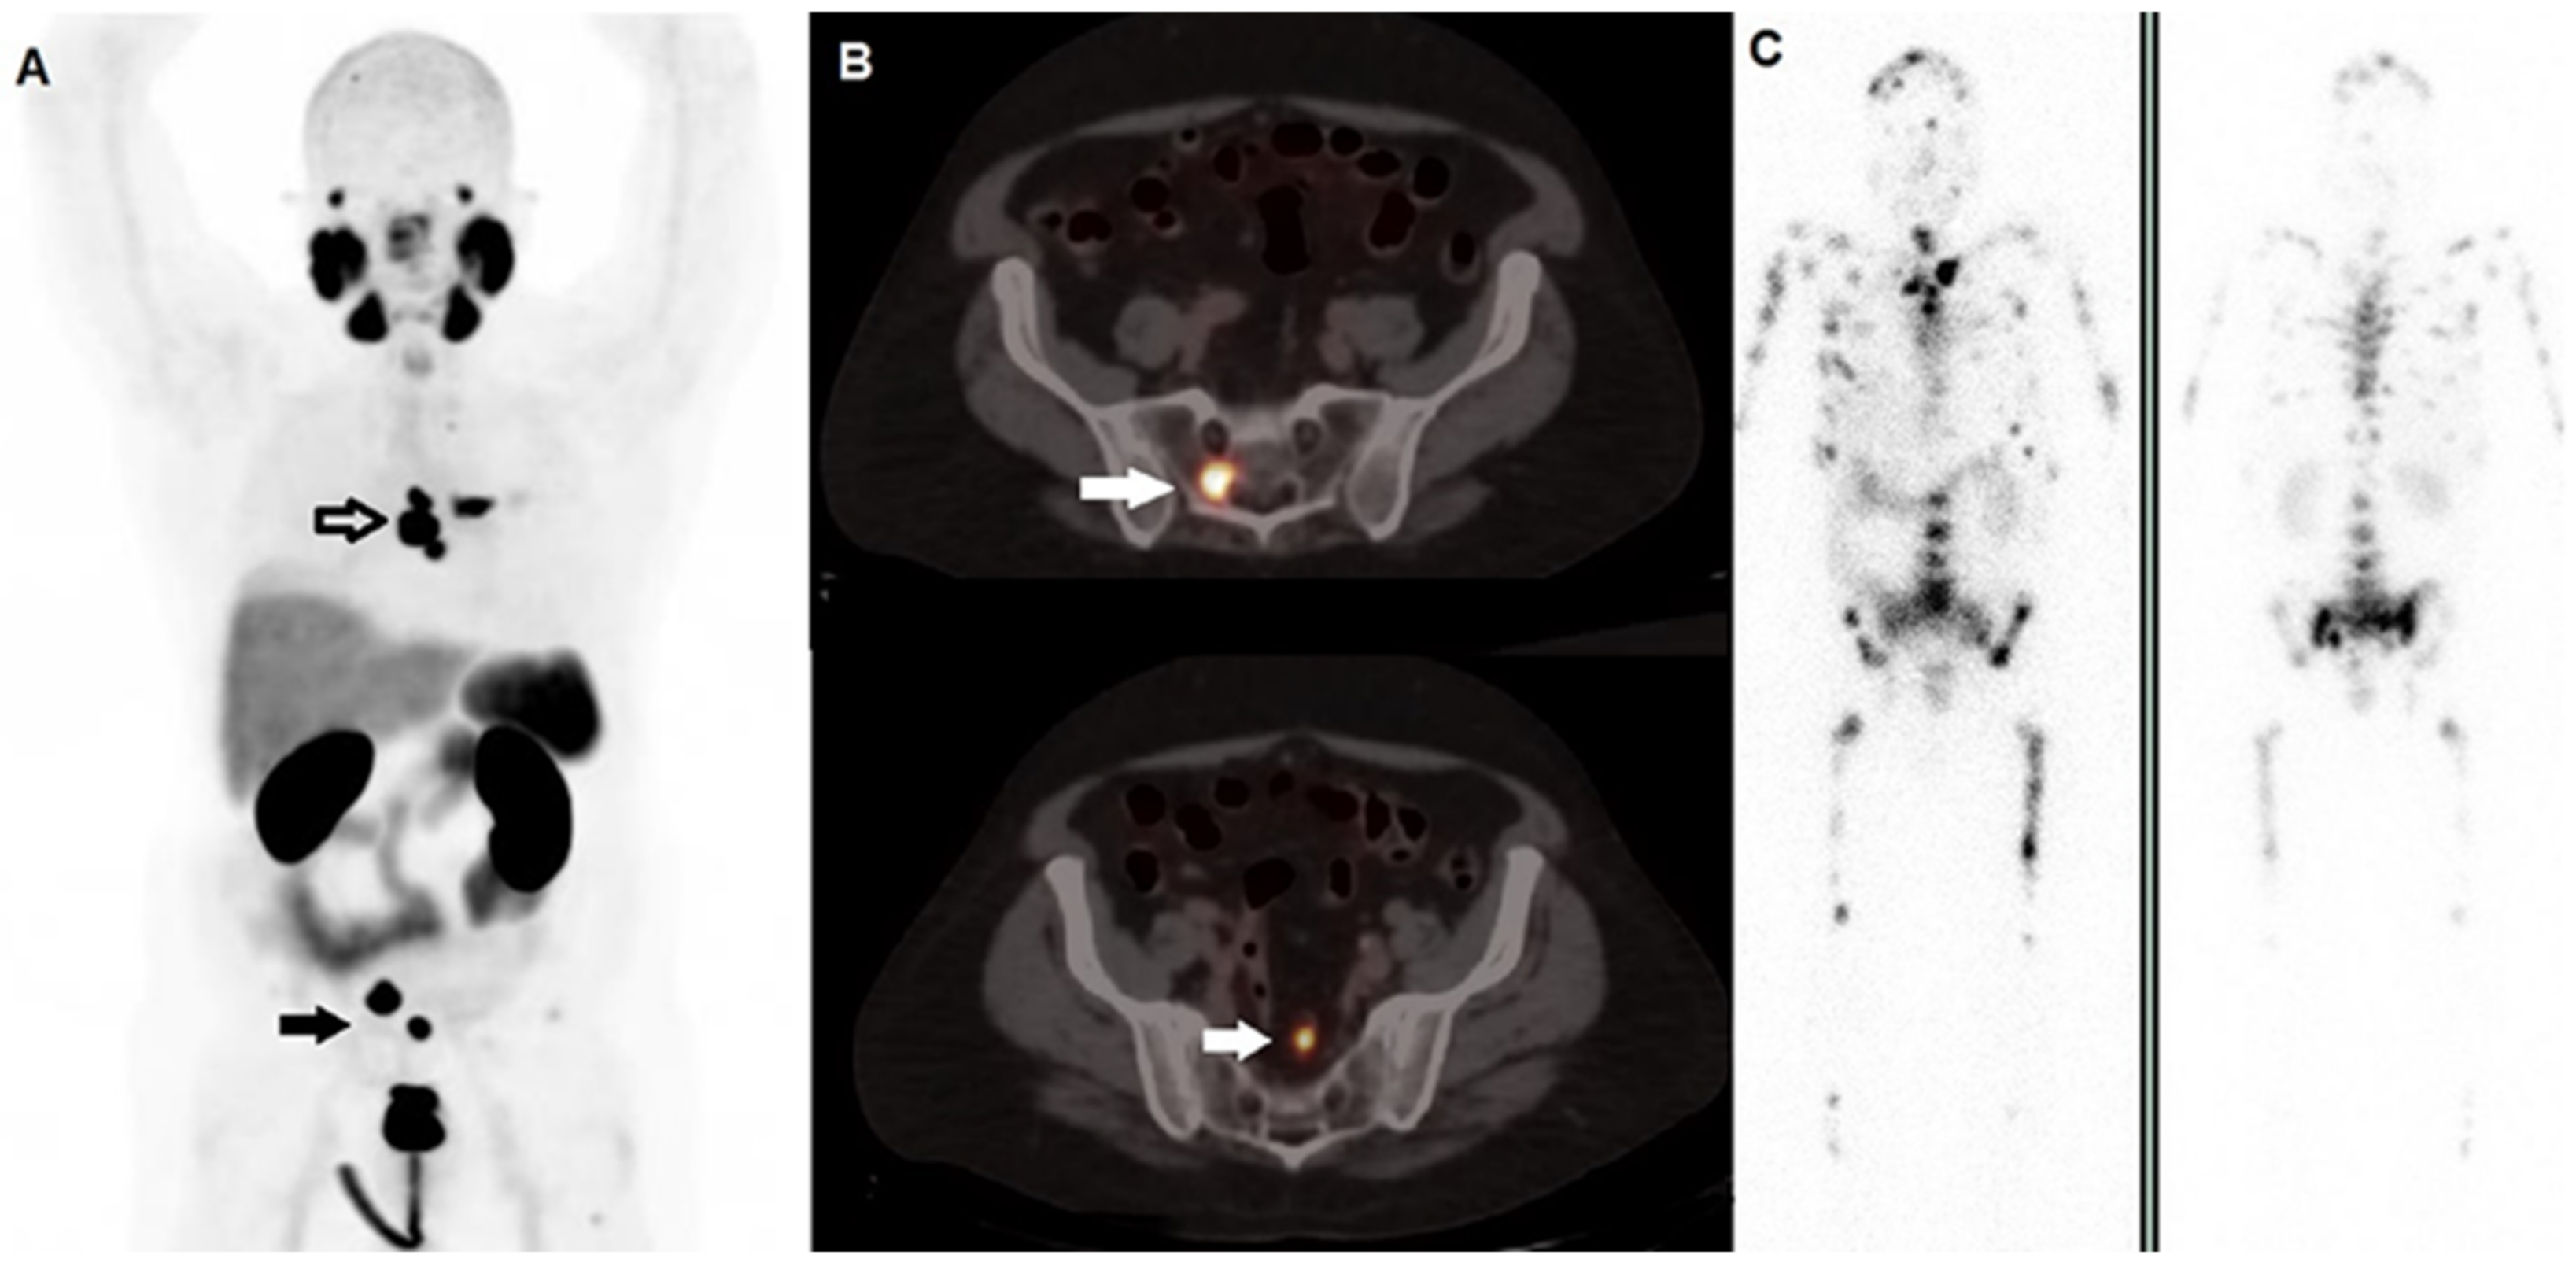

Figure 1.

A 59-year-old man affected by prostate cancer, diagnosed in 2016 and submitted to prostatectomy (Gleason score 4 + 5, ISUP 5, pT3b pN1), subsequently treated with adjuvant androgen deprivation therapy. After 2 years, progressively increasing values of PSA were registered, and the patient underwent 2nd generation anti-androgen therapy with abiraterone and, due to progressive skeletal disease, chemotherapy with taxanes. (A) Whole Body 68Ga-PSMA-11 PET/CT demonstrated highly increased tracer incorporation within metastases in the thorax (black bordered arrow) and pelvis (black arrow). (B) Fused PET/CT axial images well depicted PSMA-avid lesions in sacrum (upper row, white arrow) and in a pelvic node (lower row, white arrow). Two months later, he underwent radioligand therapy with 177Lu-PSMA-617; PSMA PET/CT was not repeated due to the shortage of tracer’s availability. (C) Whole planar images (left side; anterior view, right side: posterior view) carried out by scintigraphy on 177Lu’s photopeaks after the 1st cycle of 177Lu-PSMA-617 showed multiple sites of tracer incorporation with a much more extensive skeletal metastatization than that revealed by PET/CT. This discrepancy might be explained by the too long interval of time occurred between the diagnostic phase and the therapeutic procedure in a subject with rapidly progressive disease.